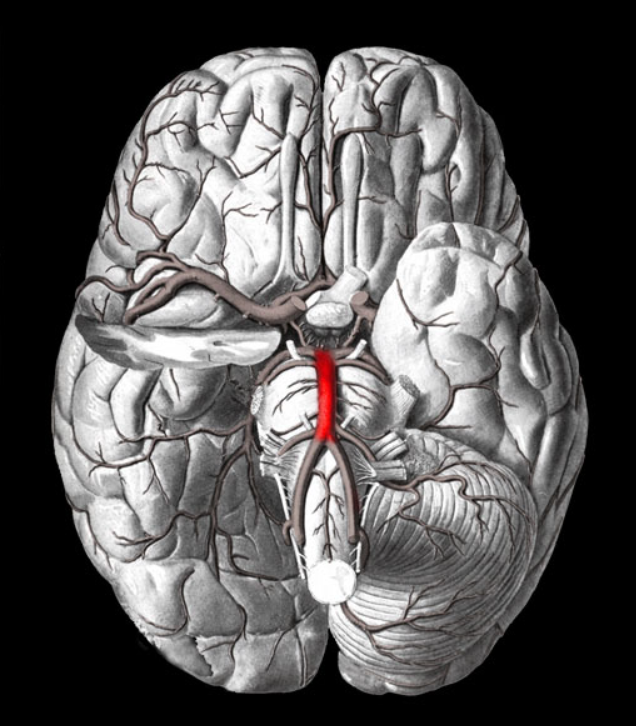

vertebral arteries

New cards

Basilar artery

10

New cards

internal carotid arteries

11

New cards

Arterial circle